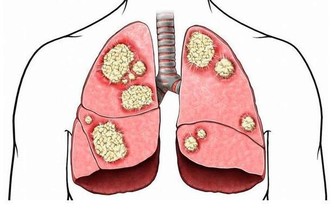

根據衛福部公布的民國103年十大死因,癌症連續33年蟬聯榜首,

占約所有死亡人數3成,平均每11分24秒就有一人死於癌症。

其實癌症發生的主要原因在於我們把食物吃下肚後無法排出體外的殘留物質,

這些老廢物質一旦堆積久了酸化後產生活性氧物質,便引發各種疾病。